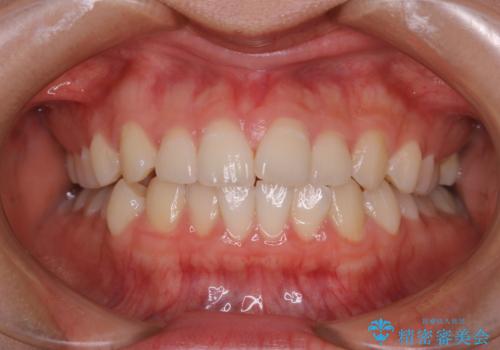

全体のガタガタをインビザラインできれいな歯並びへ